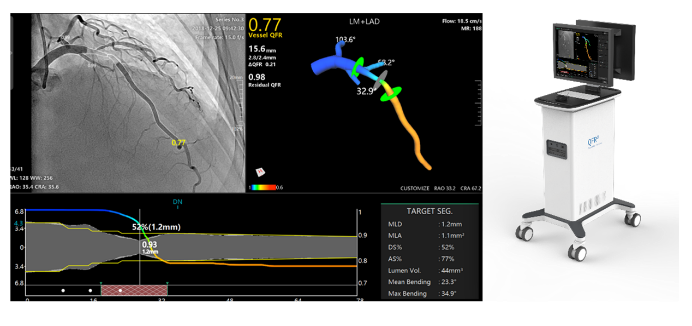

涂圣贤团队研制了一种基于冠脉影像评估血管生理功能的定量血流储备分数检测仪。系统可安装在医院介入导管室,通过网络获取导管室造影机采集的造影影像或血管内成像影像,实现快速冠状动脉三维重建与血流储备分数计算(含QFR、OFR与UFR),用于在线判断重建血管的解剖参数与功能缺血状况,以优化支架植入手术。

相关技术已完成临床转化,并通过国家药监局创新医疗器械特别审批获得三类医疗器械注册证,是国内计算生理功能学领域首个获批上市的三类医疗器械产品,并获得欧盟CE认证上市。目前,该技术已在美国、德国、日本、韩国等超300家知名医院安装使用,逐步在全球建立了冠脉生理学评估的新标准。

QFR界面示意 |